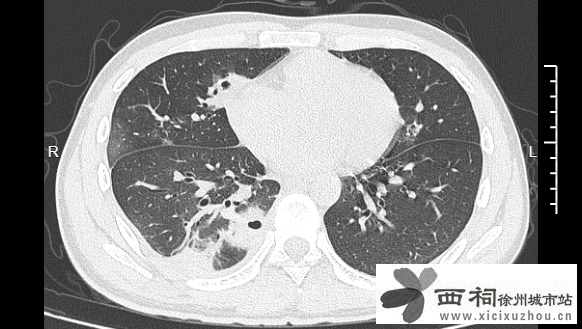

熬到第三天,小林已经烧到39℃,赶紧来到宁波大学附属第一医院就诊。接诊的丁群力主任医师一看他的症状,立刻安排了CT检查。结果显示:小林的肺里有十几个空洞,部分肺组织已经坏死,这是典型的血源性肺脓肿。

小林的CT影像显示肺里有多个空洞